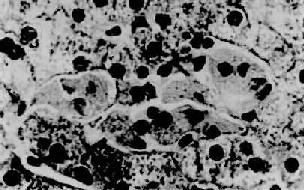

高雪(Gaucher)病,也称脑苷脂沉积症,是由于常染色体隐性遗传所致体内β-葡萄糖苷酶缺乏而引起的脑苷脂分解代谢障碍。主要累及肝、脾、淋巴结及骨髓等单核吞噬细胞系统。常发生在婴儿,为致命性疾病。主要病变为肝、脾肿大,脾大尤为明显,可达正常脾重的20倍。镜下,肝内聚集大量高度胀大的载脂巨噬细胞,有的胞浆呈泡沫状,有的胞浆出现红染条纹,后者排列成皱纹纸样外观,胞核小,圆形或椭圆形居于细胞中央,称为高雪细胞(图10-33)。这些细胞主要分布于小叶中央静脉附近的肝窦内和汇管区。偶见发生肝纤维化和肝硬化。

图10-33 高雪病之肝

图中央区为数个高雪细胞,位于肝窦内胞浆呈皱纹纸状外观